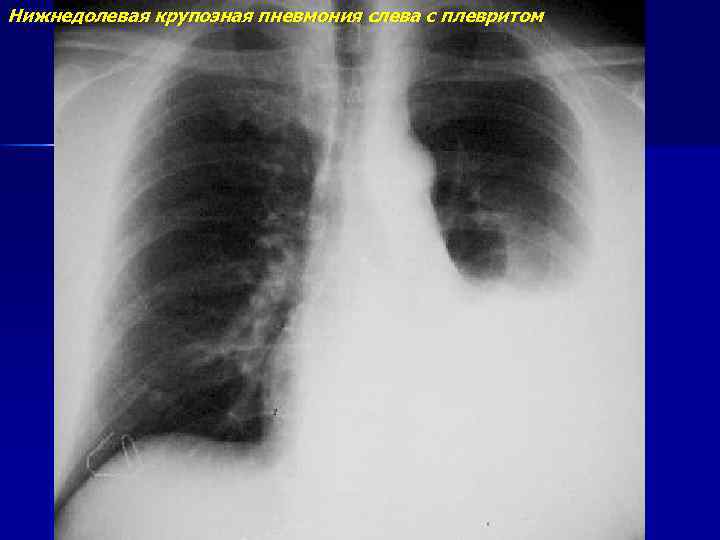

Нижнедолевая крупозная пневмония слева с плевритом